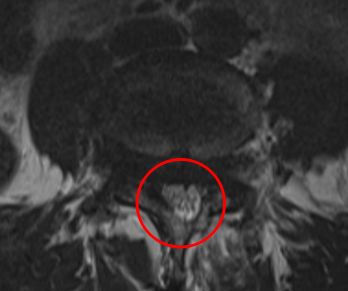

治療前

┃検査・診断

腰椎MRIを確認したところ、赤い枠で示されているL4/5 腰部脊柱管狭窄症、すべり症が見られました。特にL4/5脊柱管狭窄症に強く狭窄を認めました。

またこの腰部脊柱管狭窄症は、腰部すべり症が原因であると考えられます。